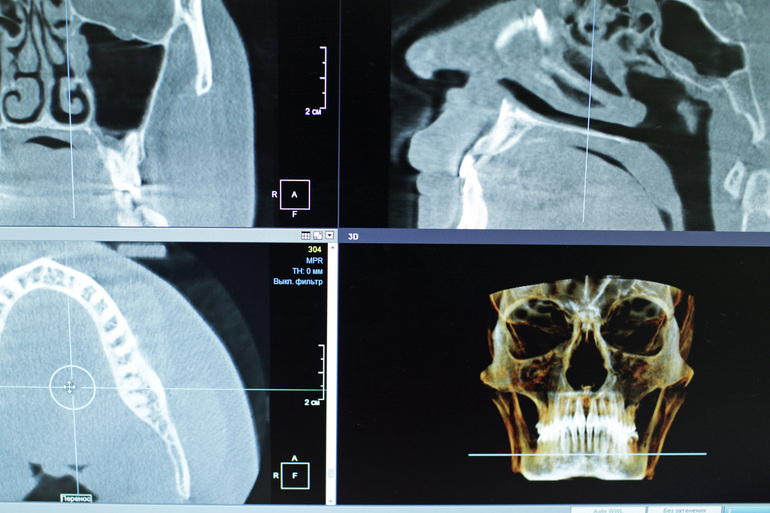

- Ветеранам операции, которые в ходе боевых действий получили ранения в челюстно-лицевую область и остро нуждаются в стоматологической помощи.